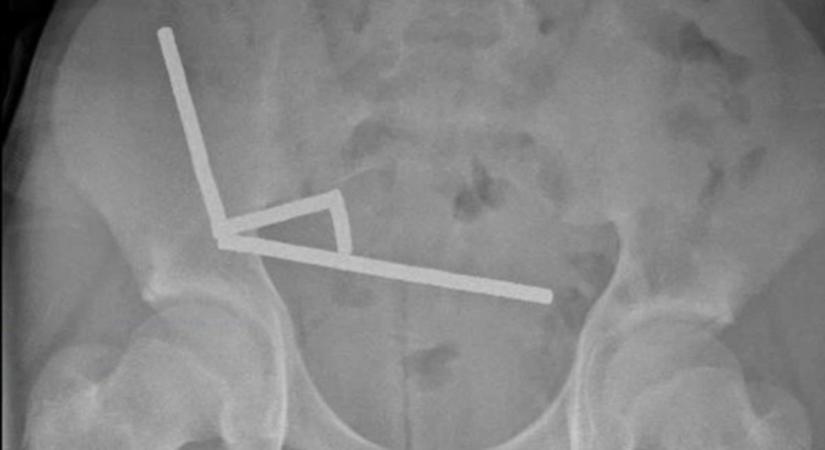

Életmentő műtéten esett át egy új-zélandi tinédzser, aki veszélyes online kihívást teljesített. A tizenéves közel 200 mágnest nyelt le, azok azonban összekapcsolódtak a beleiben, és szövetelhalást okoztak.